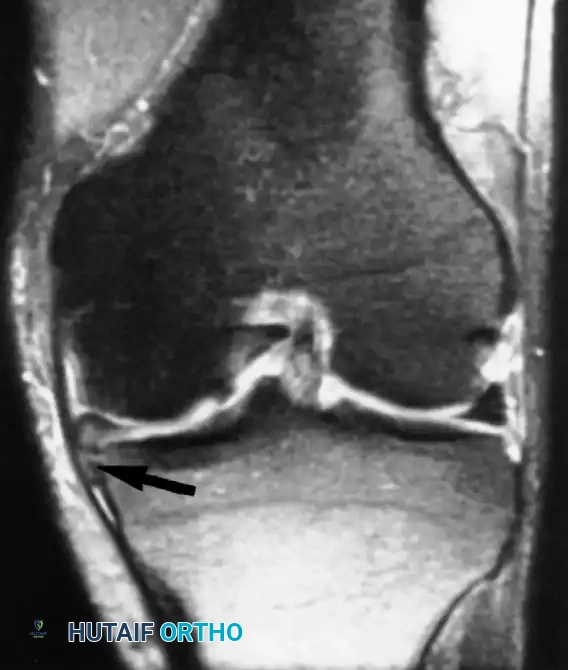

تشخيص إصابات الرباط الصليبي

الرباط الصليبي الأمامي هو المانع الرئيسي لانزلاق عظمة القصبة للأمام. يصور الرنين المغناطيسي بدقة التمزقات الحادة في هذا الرباط، والتي غالبا ما تظهر باتجاه أفقي غير طبيعي للألياف، مع وجود كدمات عظمية مميزة في عظمة الفخذ والقصبة نتيجة اصطدامهما وقت الإصابة.

كما يستخدم الرنين المغناطيسي لتقييم الأربطة الصليبية الخلفية والأربطة الجانبية لضمان سلامتها، وهو أمر حيوي قبل التخطيط لأي جراحة معقدة.